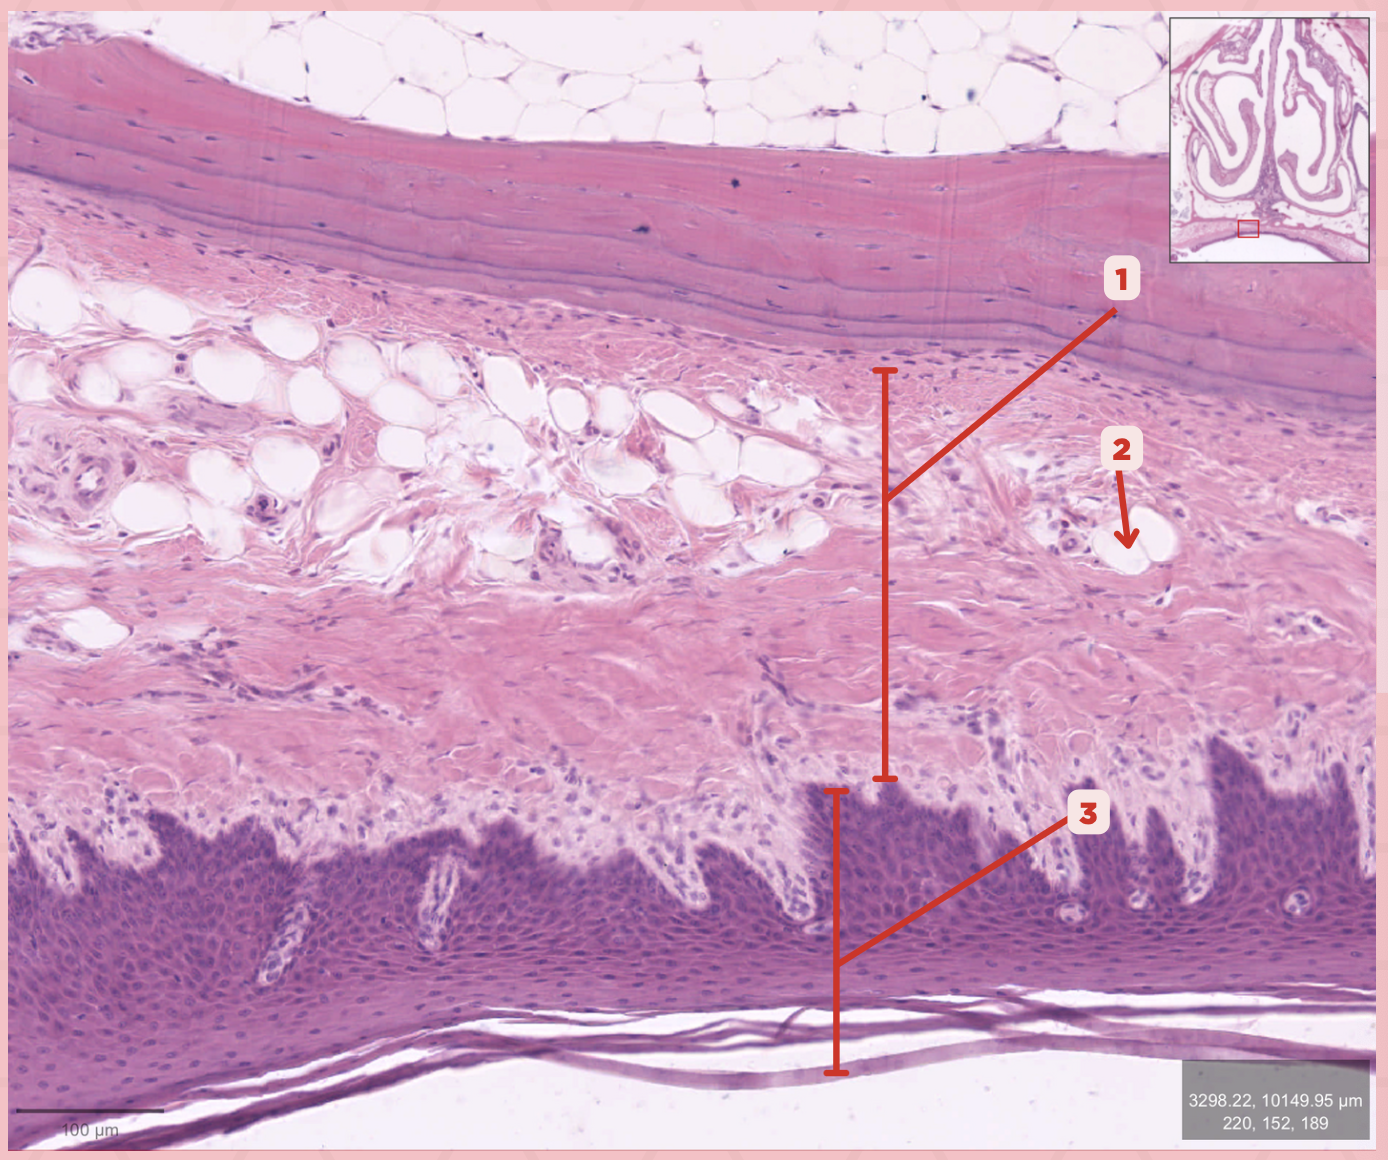

Lamina Propria

Identify the structure labeled as 1.

Adipocytes

Identify the structure labeled as 2.

Keratinized stratified squamous epithelium

Identify the structure labeled as 3.

Mucosa

Identify the structure labeled as 1.

Submucosa

Identify the structure labeled as 2.

Mucous gland

Identify the structure labeled as 3.

Serous gland

Identify the structure labeled as 4.

Loose connective tissue

What type of connective tissue comprise no. 3?

Adipocytes

Together with blood vessels and nerves, these cells are abundant in no. 3.